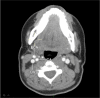

Malignant Shamblin III Carotid Body Tumors Resected with Use of the Retrocarotid Dissection Technique in 2 Patients

Carotid body tumors are rare neoplasms with malignant potential in 6% to 12.5% of cases, and surgical resection is the only cure. We present the cases of 2 female patients who had expanding, painless, right-sided neck masses; computed tomographic angiograms revealed Shamblin III tumors at the carotid bifurcation. Each patient underwent tumor resection with use of the retrocarotid dissection technique. The tumor specimens were histologically consistent with malignancy, and free margins were achieved. The patients remained free of symptoms, local recurrence, and metastasis 44 and 19 months after their respective procedures. These are the first malignant Shamblin III carotid body tumors that we have resected by means of retrocarotid dissection. In addition to our patients' cases, we discuss carotid body tumors and compare the retrocarotid and standard caudocranial resection techniques.